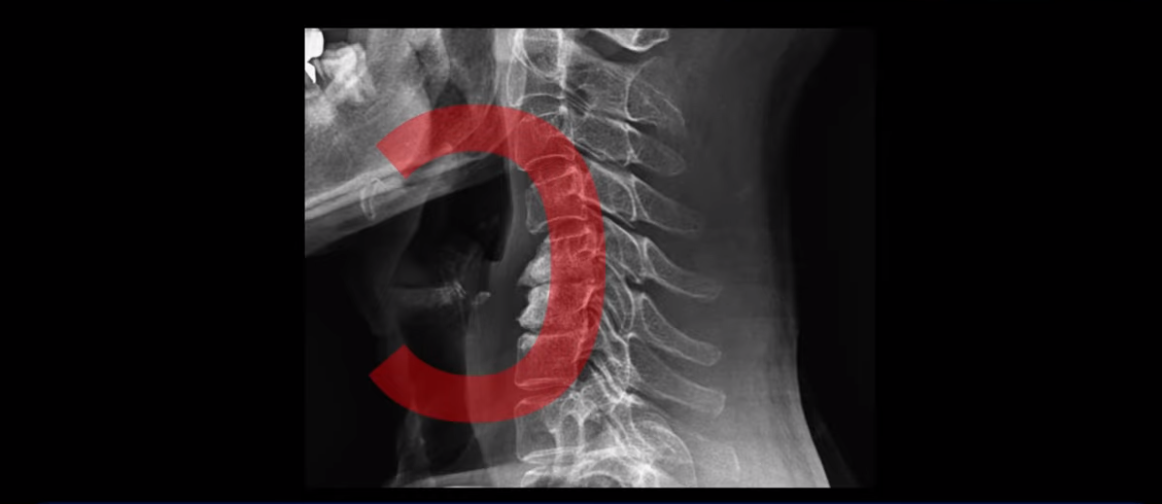

이분 목 X-ray를 보면 역C자형의 목에 전방전위도 보이고,

두 마디의 디스크가 거의 닳아서 뼈들이 거의 붙어 보입니다.

목도 많이 휘어 보입니다.